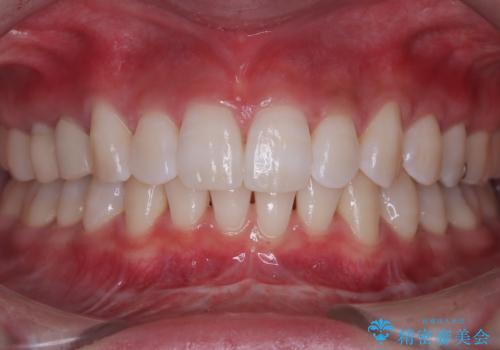

[ 矯正治療 ] 噛み合わせ前歯の見た目をきれいにしたい

![[ 矯正治療 ] 噛み合わせ前歯の見た目をきれいにしたいの症例 治療前](https://seimitsushinbi.jp/wp/wp-content/uploads/2025/08/IMG_7266-500x350.jpg?v=1754654745)

![[ 矯正治療 ] 噛み合わせ前歯の見た目をきれいにしたいの症例 治療後](https://seimitsushinbi.jp/wp/wp-content/uploads/2025/08/IMG_3482-500x350.jpg?v=1754654765)